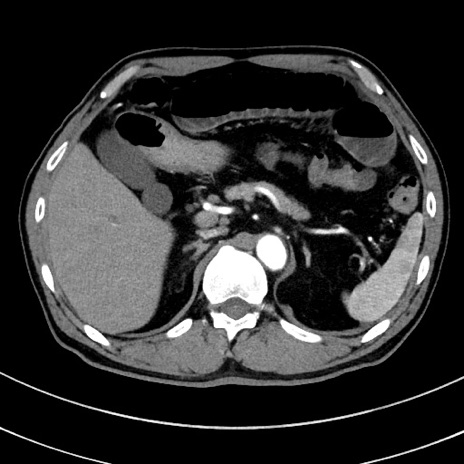

症例8(横断像)

【症例】 60歳代男性

【主訴】 黒色吐物

【現病歴】 4日前から嘔気自覚、2日前の朝食後にも嘔気あり、自分で手で嘔吐反射起こし嘔吐したところ血が混ざっていたため受診。

【既往歴】 5年前汎発性腹膜炎を伴う急性虫垂炎で手術、高血圧、前立腺肥大症、高脂血症

【身体所見】 腹部正中に手術癩痕あり 腹部平坦・軟圧痛なし膨満感あり

【データ】WBC 8400、CRP 4.54